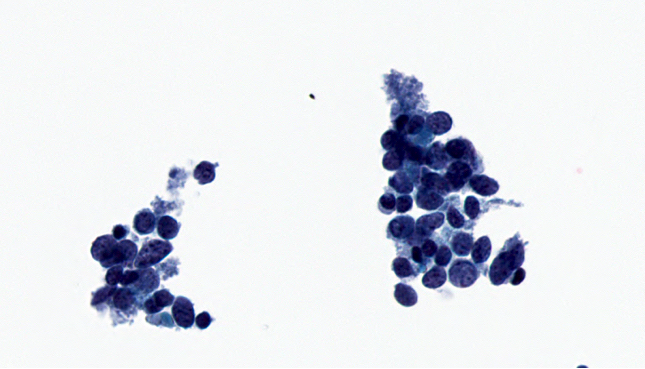

Cytology description

- Hypercellular specimen featuring small to medium sized neoplastic cells, dispersed and arranged in cohesive, disorganized groups with nuclear molding

- Neoplastic cells display uniform, round / oval nuclei with fine stippled chromatin, inconspicuous nucleoli, scant cytoplasm and high N:C ratio

- Apoptotic bodies, necrotic debris and mitoses are frequent

Cytology images